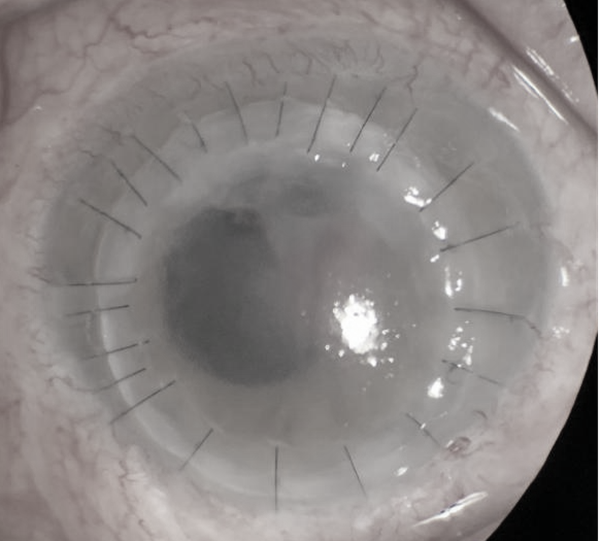

近日,我院眼科马君择副教授、王剑超主治医师在王峰主任的指导下,成功为一位严重真菌性角膜溃疡患者完成了穿透性角膜移植手术。

患者系49岁男性,右眼眼红、轻微眼痛、伴畏光流泪1月,加重10天,外院保守治疗效果不佳,病情加重,慕名来到我院马君择副教授门诊求诊。经过仔细询问病史以及眼科常规裂隙灯检查后,马君择副教授以“右眼真菌性角膜溃疡、右眼前房积脓”之诊断将患者收住入院。

入院时患者右眼视力仅有眼前手动,立即行角膜清创,予局部抗真菌药物点眼,辅以促进生长、散瞳、抗炎等治疗,病情一过性好转,视力恢复至眼前指数,但由于患者病程长,真菌感染已穿透角膜深入前房,遂行结膜瓣遮盖术,但因角膜溃疡炎症反应强烈,术后5天,结膜瓣完全溶解。患者眼后节未见明显异常,行角膜移植术可清除感染灶,恢复部分视力,与患者充分沟通后,患者同意行角膜移植术。随后马君择副教授团队经术前周密计划,术中与手术室密切配合,为患者顺利施行了角膜移植术。术后继续抗真菌、抗排斥反应、促进角膜生长治疗,病情好转,顺利出院。出院时患者裸眼视力0.06,2周后复查,恢复良好,裸眼视力0.1,患者十分满意。